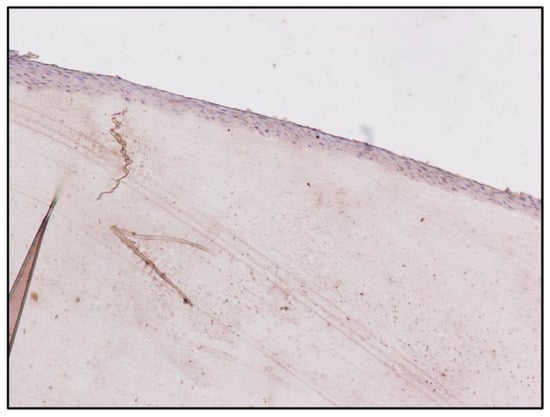

| Fingernail matrix | Area | Mean |

| Subject B (Figure 2) | 1,228,800 | 26.049 |

| Subject C (Figure 5) | 1,228,800 | 2.252 |

| Subject B matrix | Instrument | Morphine | 6-MAM | Codeine | Methadone | EDDP |

| Blood | GC-MS | 360 ng/ml | Negative | Positive | Positive | Positive |

| Pubic hair | UHPLC | 1.60 ng/mg | 0.44 ng/mg | Positive | Positive | Positive |

| Fingernail | UHPLC | 1.23 ng/mg | 1.18 ng/mg | Positive | Positive | Positive |

| Subject C matrix | Instrument | Morphine | 6-MAM | Codeine | Methadone | EDDP |

| Blood | GC-MS | Negative | Negative | Negative | Negative | Negative |

| Pubic hair | UHPLC | 2.2 ng/mg | 4.43 ng/mg | Positive | Positive | Positive |

| Fingernail | UHPLC | Negative | 1.03 ng/mg | Negative | Negative | Negative |